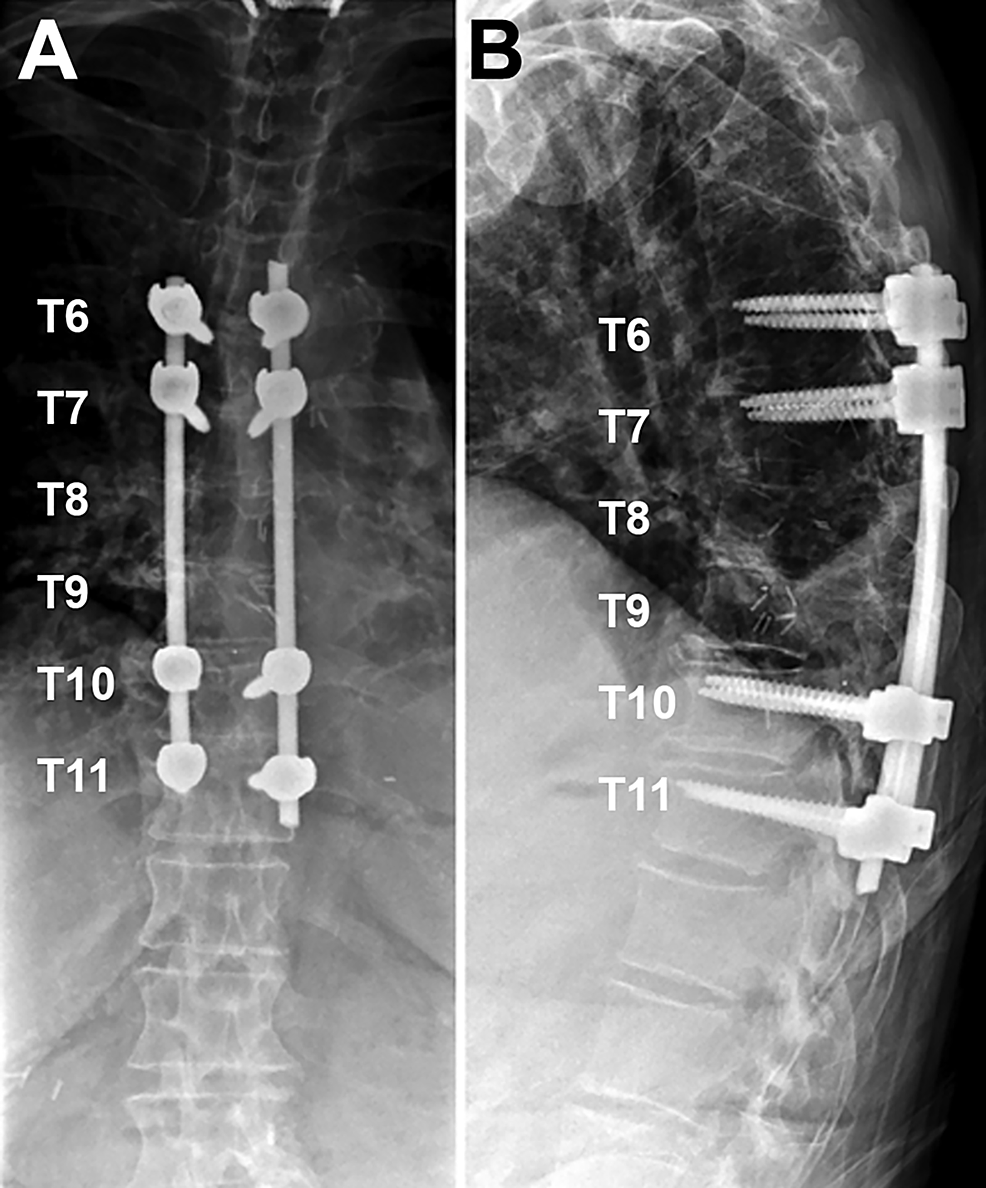

From www.researchgate.net

Preoperative posteroanterior fulcrumbending xray of thoracic spine Bolster View X Ray The bolster should be placed at the exact location (the level of painful cemented vertebra) on the back before lying down. Purpose and structures shown a basic view of the thoracic spine showing all 12 thoracic vertebral bodies, intervertebral disc spaces, transverse processes, and. The radiograph should be centered on the painful cemented vertebra. Rapid identification of spinal injuries requiring. Bolster View X Ray.